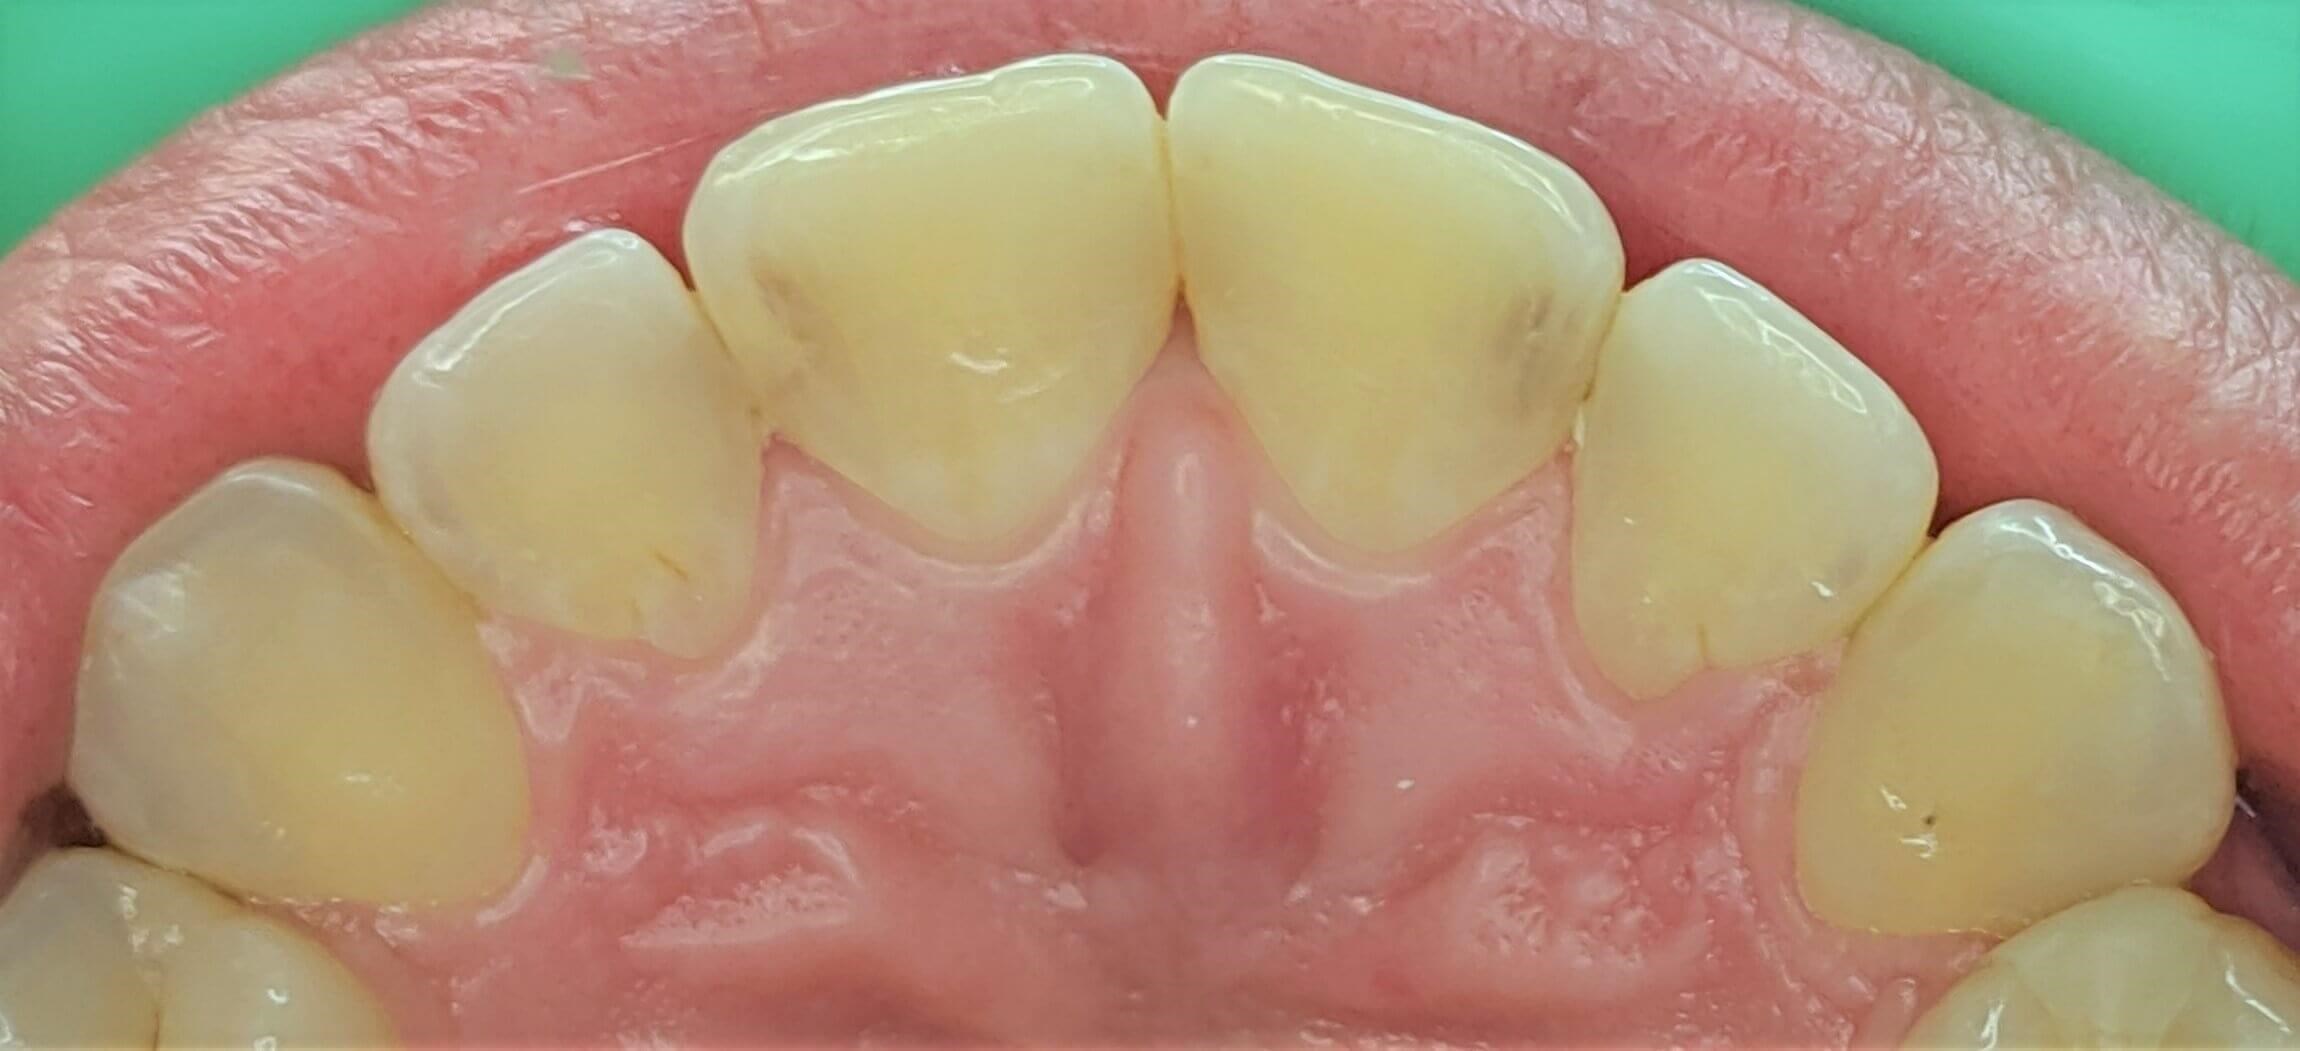

Tooth-colored fillings often fill in the decay in the enamel after it has been cleaned. Composite resin is a versatile material that can be used to treat other problems with your teeth, including cracks or enamel that has been worn down by teeth grinding (bruxism). Since the composite resin is colored to match your natural teeth, tooth-colored fillings can be used on both the front and back teeth for a seamless appearance. If you have metal fillings, talk to Dr. Kim or Dr. Chang about having them removed and replaced with tooth-colored fillings.

Getting a filling at Luminous Dental Studio is typically an easy process. The area surrounding the cavity will be numbed with a local anesthetic to minimize your discomfort. Other forms of sedation can be discussed if you have any fears or dental anxieties to help keep you at ease during the procedure. Once you are prepared, the decayed enamel is removed with a unique dental drill that Dr. Kim or Dr. Chang will select based on where the cavity is located in the tooth and the level of decay. After the enamel is removed and the tooth is cleaned, the cavity will be filled with the composite material and set with a special light. Dr. Kim or Dr. Chang will polish the filling so it feels comfortable and matches your natural teeth.

Yes, they do. The main benefit of tooth-colored fillings is the fact that they don't change the natural color of your tooth — so no one but you will know you have a filling.